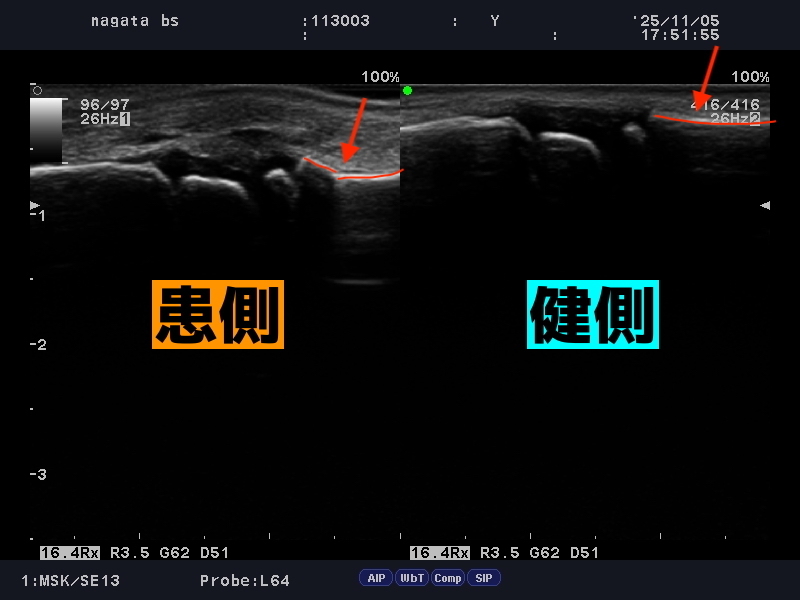

骨折の変形で小指が外側を向いていいます。

外観上、指は変形し外側を向いてしまうほどの重度の骨折です。

本人は、そんなに痛くないよと言っていましたが、明らかに骨折を認めます。当院では見逃しません。

左右を比較すると骨折による変形が確認できます